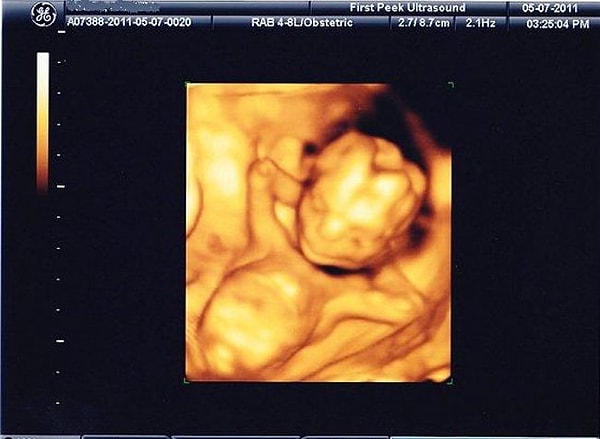

2. "Моя пре-е-е-елесть!"